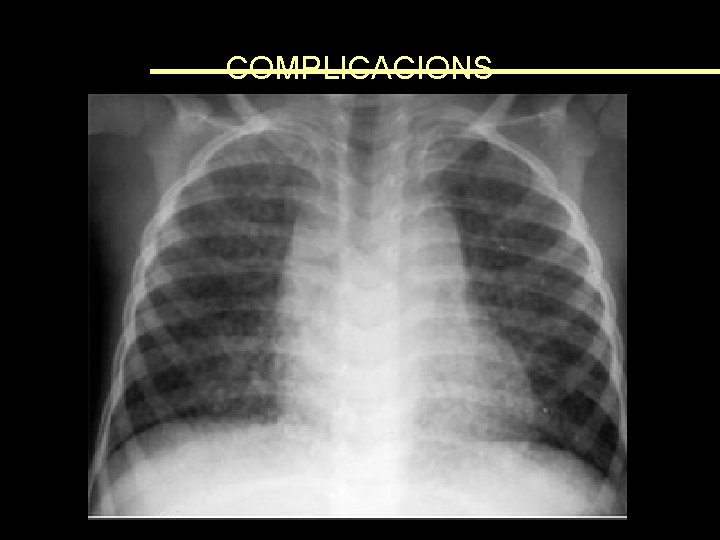

COMPLICACIONS • En països subdesenvolupats: 4 -10% • Mortalitat: majorment associada a complicacions respiratòries i encefalitis • Pacients susceptibles: – – – Immunocompromesos Embarassades Desnodrits Dèficit de Vit A Edats extremes

COMPLICACIONS